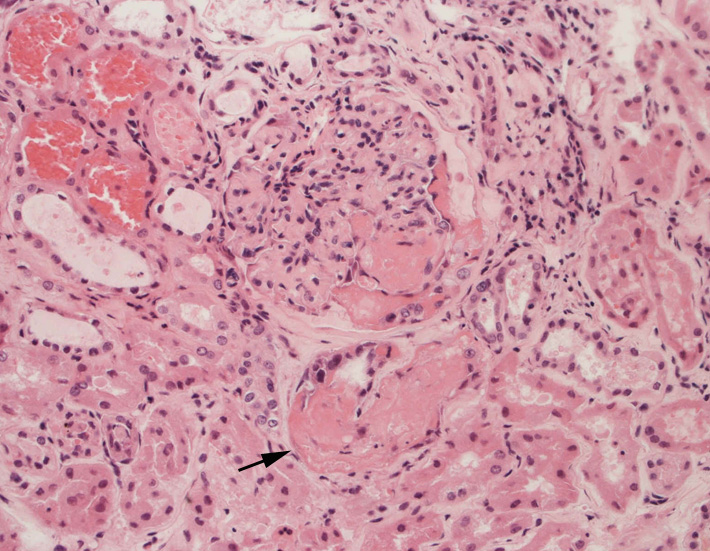

腎臓の病理組織所見-->壊死性糸球体腎炎

kidney01.jpg

kidney02.jpg

Fig.01Fig.02Fig.03

Fig.06Fig.07 尿細管壊死